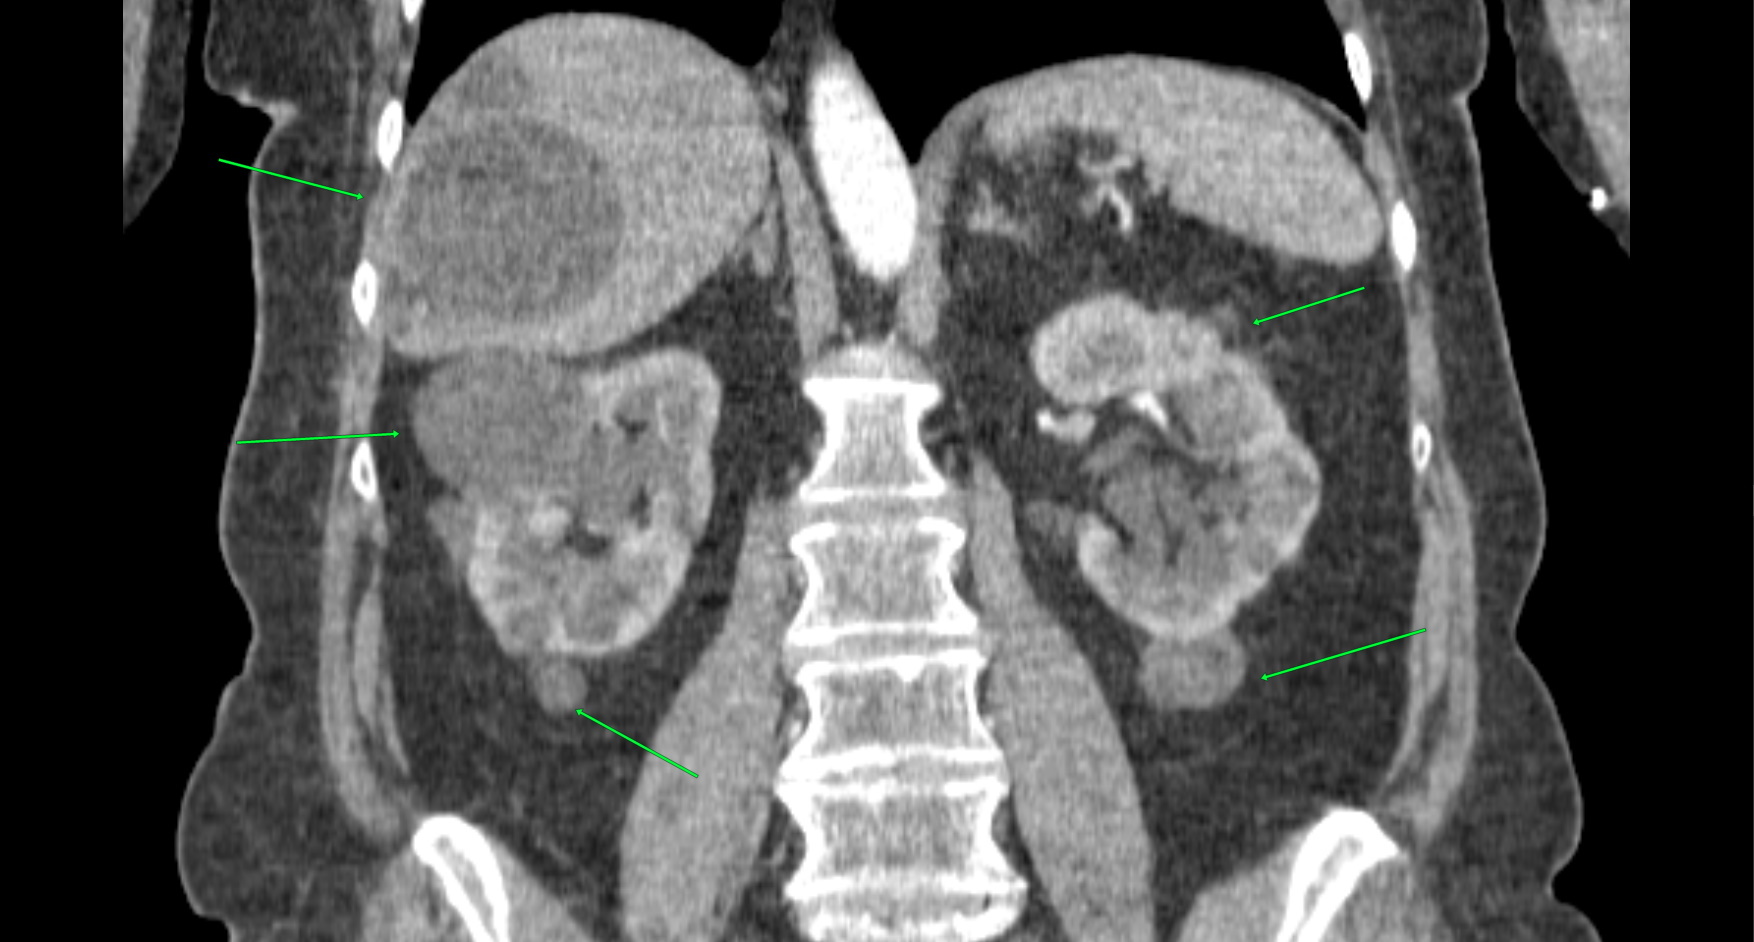

Диагностика гемангиобластомы: изображения и объяснения